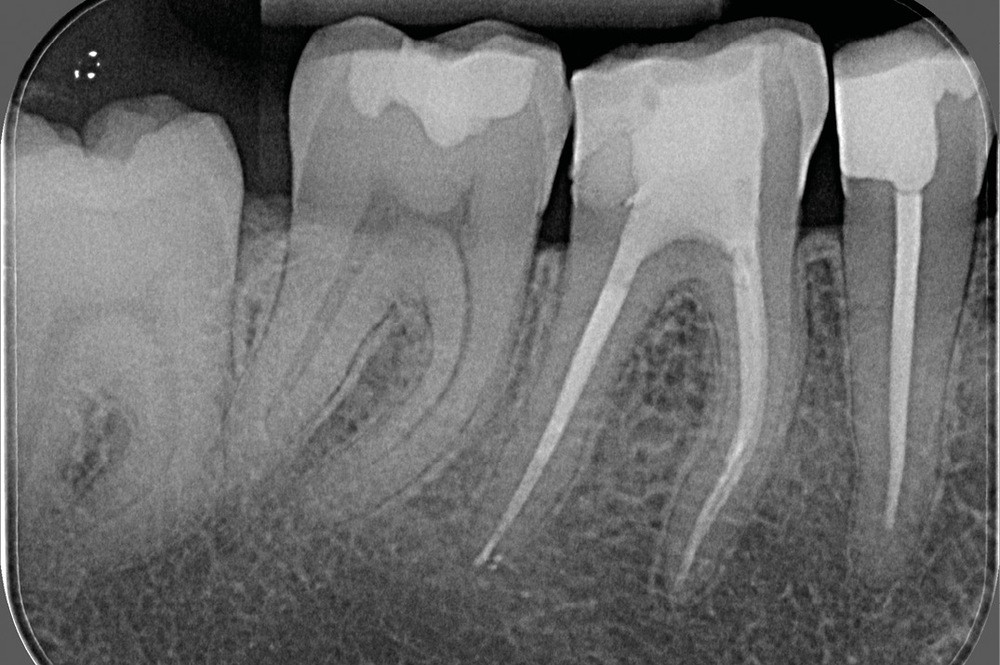

La préparation mécanique est principalement réalisée à l’aide d’instruments NiTi utilisés en rotation continue ou en réciprocité selon une approche corono-apicale. La mise en forme est ainsi plus rapide et respecte mieux le trajet canalaire initial qu’avec une instrumentation manuelle. Le diamètre apical et la conicité de la préparation canalaire font toujours débat. Ils dépendent de l’anatomie initiale et doivent permettre une irrigation efficace sans fragiliser la dent. Ainsi, un diamètre apical de 30 et une conicité de 6 % sont souvent proposés comme objectif minimal à atteindre [3] (fig. 1).